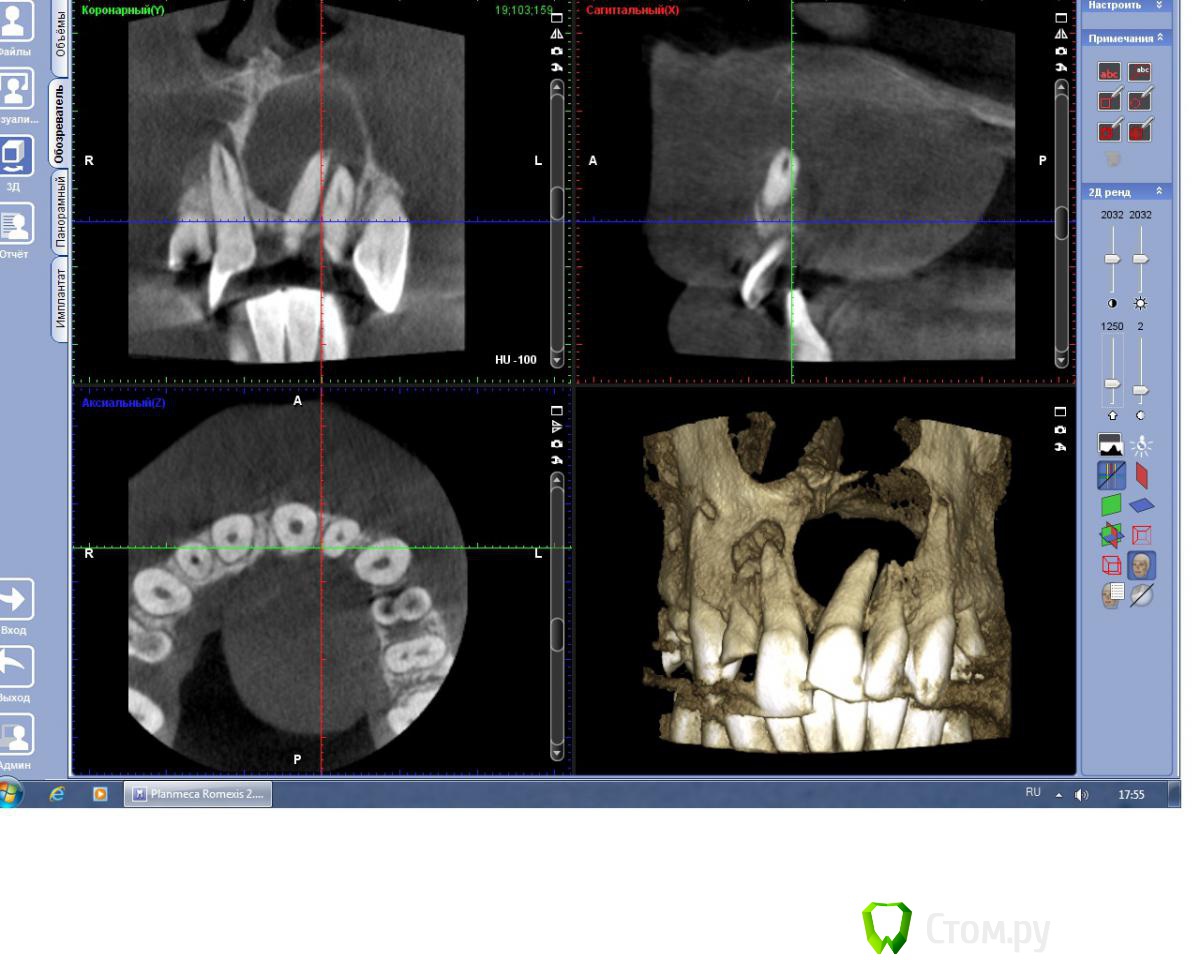

BryanDoc Опубликовано 5 февраля, 2014 Поделиться Опубликовано 5 февраля, 2014 (изменено) Пациент 25 лет обратился в клинику с нагноившейся кистой верхней челюсти слева, абсцесс передней трети твердого неба.На первом этапе проведено вскрытие абсцесса, после стихания острых явлений, установлена декомпрессионная трубка от системы с вестибулярной поверхности, и проверена витальность фронтальных зубов(Эндофрост), витальным оказался только 22 зуб, 21 и 11 зуб --апекс IRM, потом инжектор, 23-- инжектор, удалены корни 12, 24, 36 зубов проведена пародонтология, на последней КТ результат через 8 месяцев консервативного лечения.На начальном этапе подвижность 21, 11 была 3 степени, сейчас подвижности нет.У меня возник вопрос по поводу происхождения кисты? Подозрение что это носо-небная киста, по нескольким критериям---1--отклонение корня 21 зуба, располагается между 11 и 21 , и при эндодонтии 21 и 11 зубов было слизистое отделяемое в канале зубов из кисты.Доктора кто что думает на этот счет?так как дальнейшая тактика если это все таки носо-небная киста то это цистэктомия, через некоторое время. Изменено 5 февраля, 2014 пользователем BryanDoc Ссылка на комментарий

kriokov Опубликовано 5 февраля, 2014 Поделиться Опубликовано 5 февраля, 2014 У меня возник вопрос по поводу происхождения кисты? думаю, что радикулярная (воспалительная) от 21.1. очаг деструктивный в обл 21 , корень выстоит в костный дефект2. консервативное лечение 21 дало + динамику3. киста носо-небная не воспалительного генеза4. носонебный идет в обл между небными отрастками верхней челюсти и межчелюстной, т.е чаще по центру располагается4. можно было бы на кт до лечения посмотреть весь канал на аксиальных срезахДумаю нормально все будет после лечения, кт в динамике , и на живучесть 22 и 13 в динамике. 2 Ссылка на комментарий

BryanDoc Опубликовано 6 февраля, 2014 Автор Поделиться Опубликовано 6 февраля, 2014 (изменено) думаю, что радикулярная (воспалительная) от 21.1. очаг деструктивный в обл 21 , корень выстоит в костный дефект2. консервативное лечение 21 дало + динамику3. киста носо-небная не воспалительного генеза4. носонебный идет в обл между небными отрастками верхней челюсти и межчелюстной, т.е чаще по центру располагается4. можно было бы на кт до лечения посмотреть весь канал на аксиальных срезахДумаю нормально все будет после лечения, кт в динамике , и на живучесть 22 и 13 в динамике. Я тоже так подумал, но 21 и 11 зуб без кариозных полостей и пломб, а пульпа в них была мертвая, точнее небыло уже к моменту раскрытия зуба.Ну а носонебная невоспалительная киста может нагнаиваться, если она дорастает до зубодесневого соединения.На КТ небной платстинки в области 21 и 11 зубов нет, поэтому канал не определяется. Изменено 6 февраля, 2014 пользователем BryanDoc Ссылка на комментарий